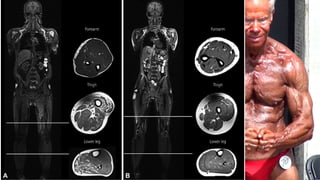

Existe un buen registro de la pérdida de masa muscular con la edad. La excreción de creatinina

urinaria, reflejo del contenido de creatinina del músculo y la masa muscular total, disminuye

aproximadamente en un 50% entre los 20 y los 90 años de edad. La tomografía computarizada de

los músculos de un individuo muestra que después de los 30 años se da una disminución en las

áreas transversales del muslo, un descenso en la densidad muscular y un aumento en la grasa

intramuscular. Estos cambios son más evidentes en las mujeres.